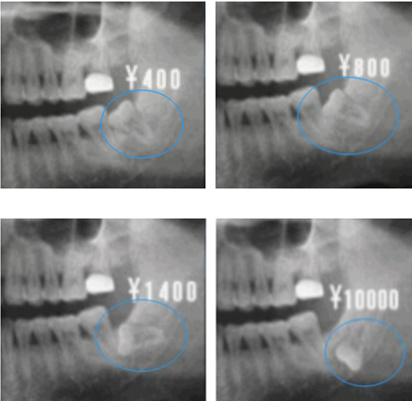

不僅(jin) 如此,智齒即便是阻生也有各種各樣的姿態:近中傾(qing) 斜(倒向鄰牙)、垂直阻生(豎著長)、遠中傾(qing) 斜(背向鄰牙)、水平阻生(橫著長)、倒置阻生(倒著長)等,通常來說,這些智齒都是不好拔牙的。

再者說,智齒根據埋在頜骨內(nei) 的深度,還可以分為(wei) 高位阻生(智齒牙冠高於(yu) 鄰牙牙冠或者一樣)、中位阻生(智齒牙冠部位低於(yu) 鄰牙牙冠但高於(yu) 鄰牙牙頸部)以及低位阻生(智齒牙冠部位低於(yu) 鄰牙牙頸部)。埋伏的深度不同,拔牙難度自然更加不同。

一般來說,比較常見的,普遍的智齒雖然拔牙難度大,但是大部分醫生都能操作的。這種智齒拔除費用一般在數百元左右,比如上頜智齒。

而臨(lin) 床上,一般下頜智齒拔除難度明顯比上頜更大,主要是由於(yu) 下頜智齒不僅(jin) “造型獨特”,方向各異,而且下頜智齒附近還有下牙槽神經,尤其是中低位阻生智齒距離下牙槽神經很近,拔牙難度更大。簡單的說,就是下頜智齒越是位置刁鑽,角度奇怪的,拔牙越難,價(jia) 格越貴。目前下頜智齒拔除一般都要上千元,甚至是兩(liang) 三千元,這都是正常的。